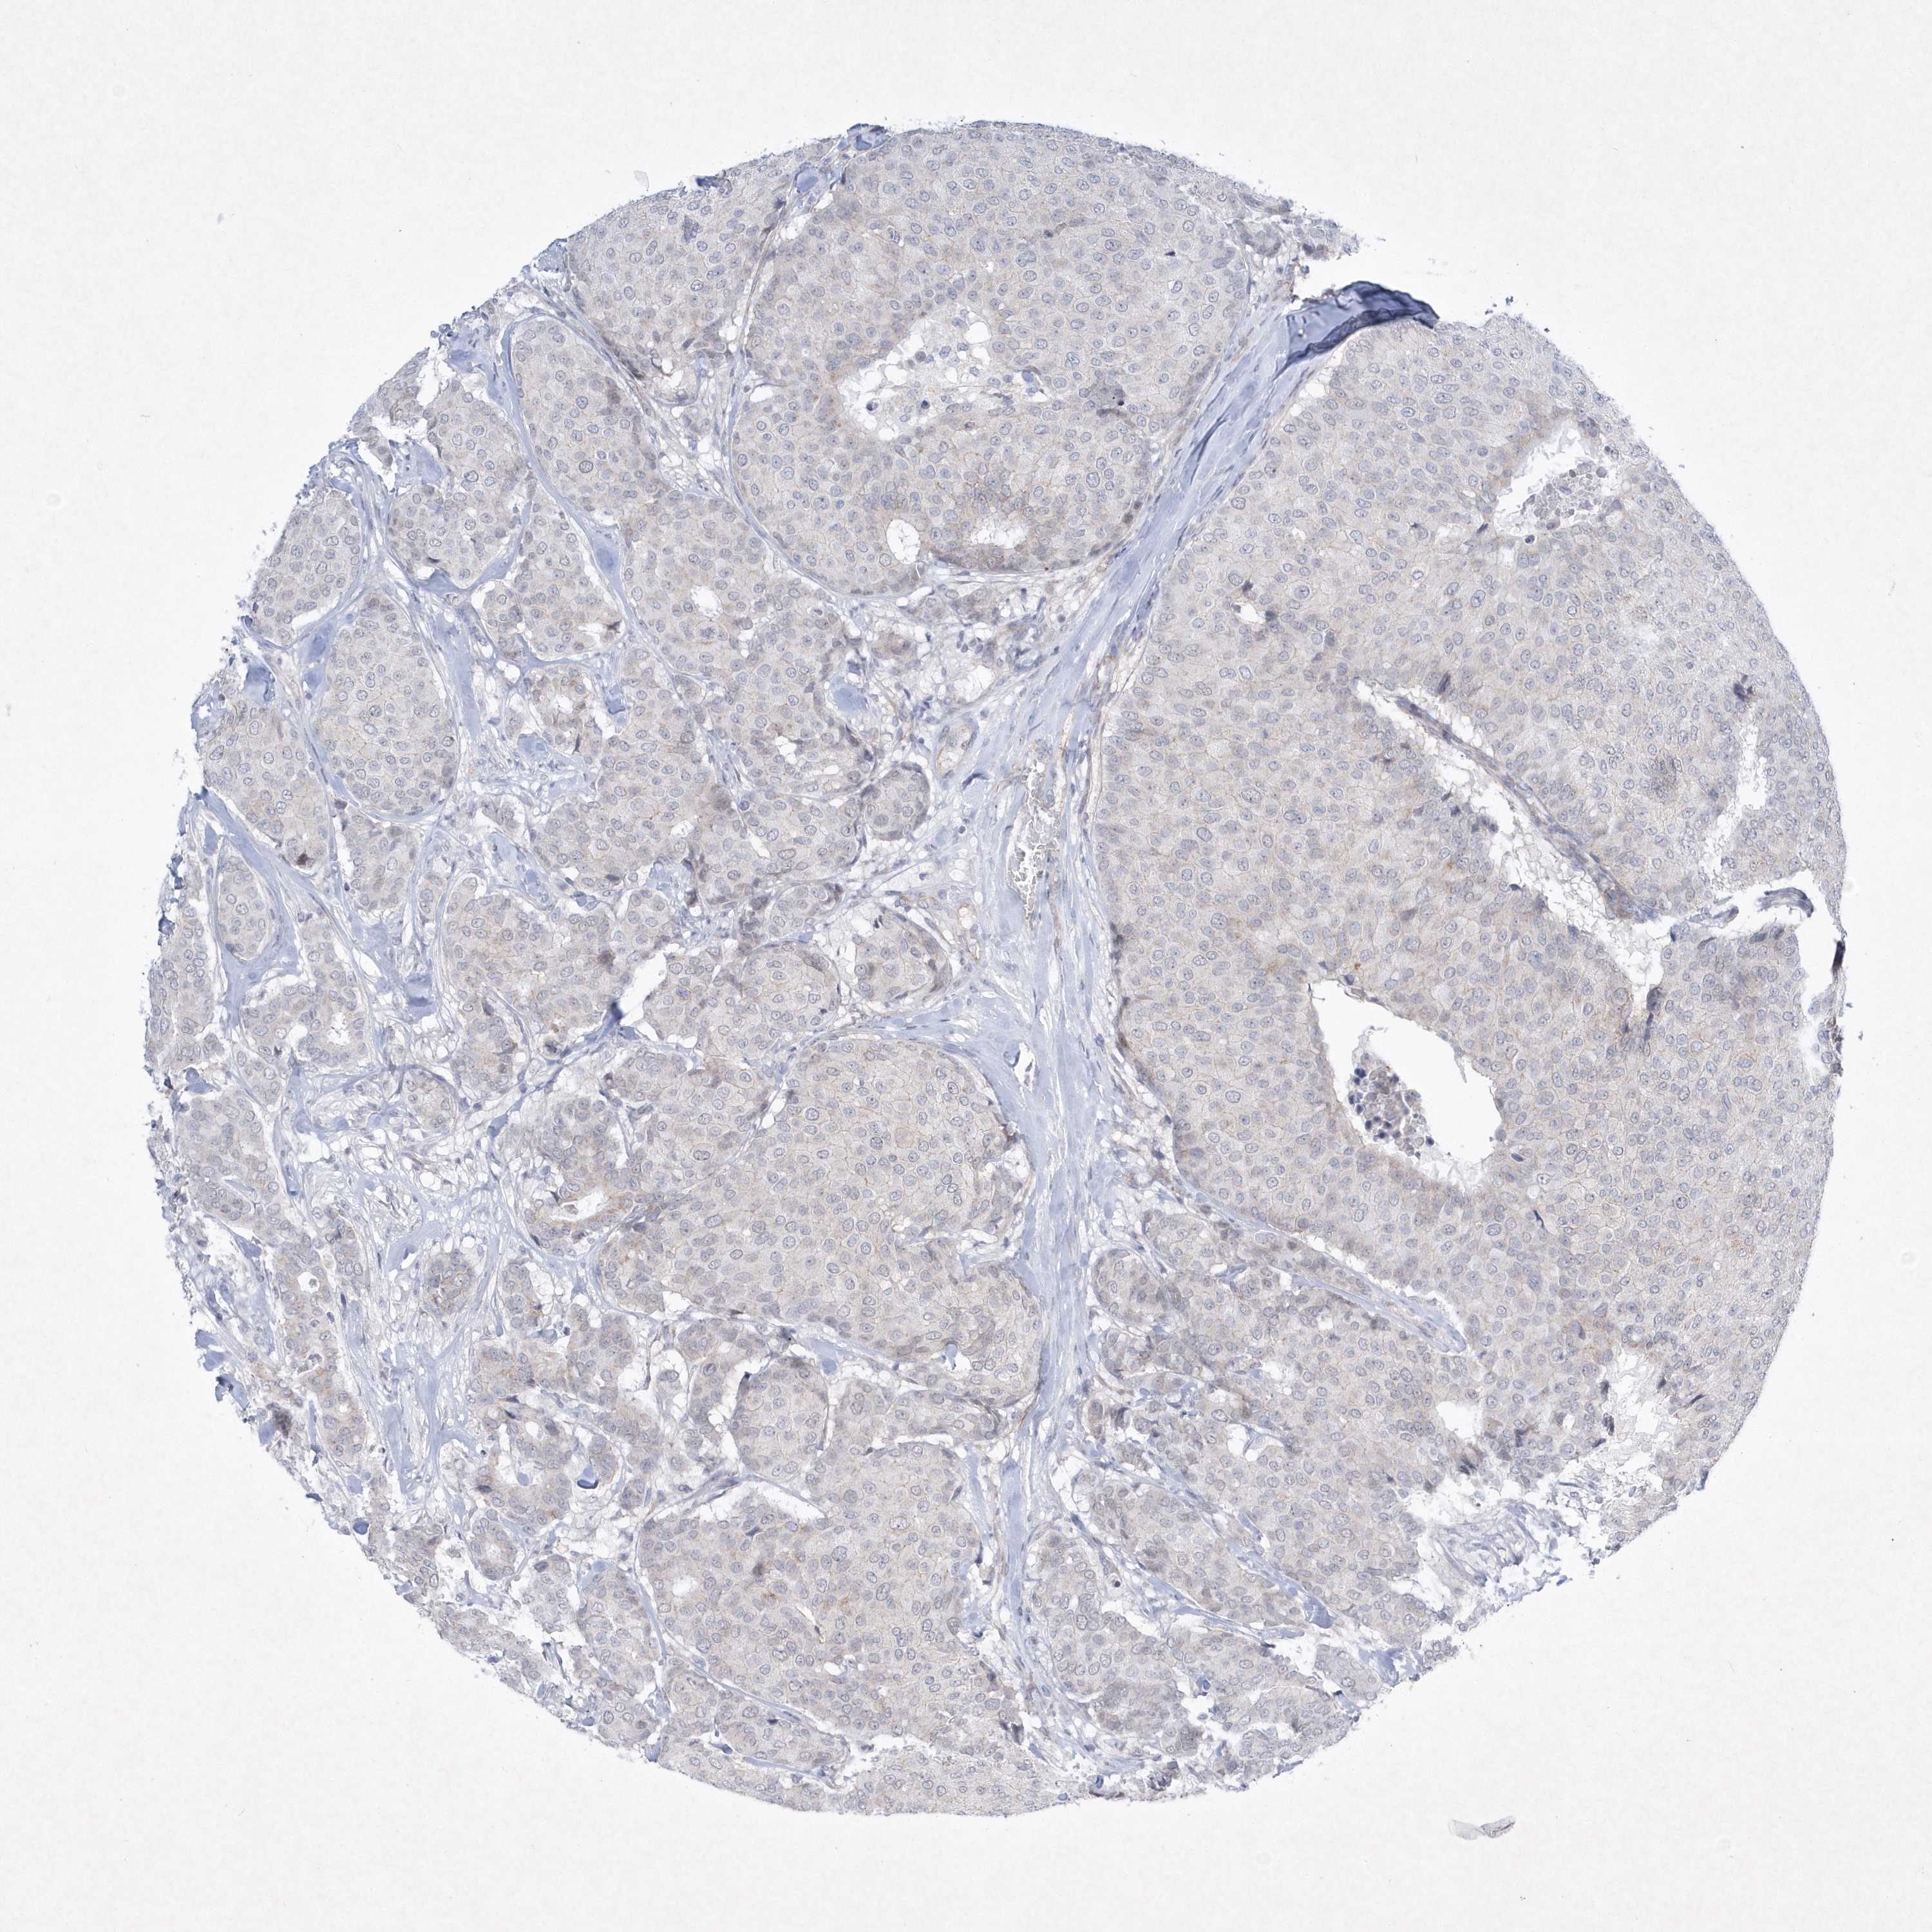

BRCA TCGA BRCA VALIDATION PROTEIN EXPRESSION